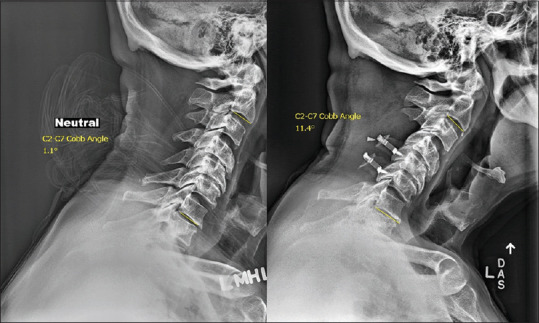

Materials and methods: We retrospectively reviewed CSM patients who underwent laminoplasty at an academic tertiary care center between January 1, 2016, and January 30, 2022, and had a complete set of anterolateral cervical X-rays at 1-year follow-up. Angular kyphosis was defined as the loss of cervical lordosis by more than - 10° after surgery when measuring the difference between pre- and post-operative C2-7 Cobb angles. Regression and receiver operating characteristic (ROC) curve analysis were used to assess the ability of the frailty assessments to predict for PKD.